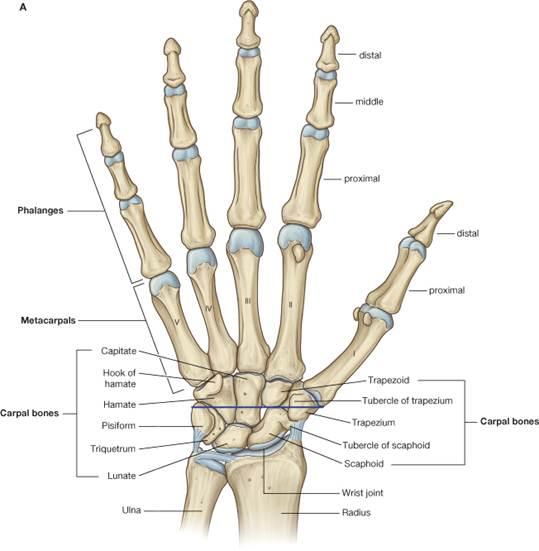

Total Wrist Fusion | Musculoskeletal Key

Arthroscopic Partial Wrist Fusion | Musculoskeletal Key

Wrist Arthrodesis: Limited and Complete | Musculoskeletal Key